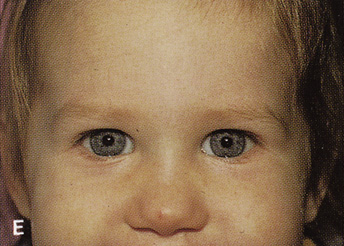

Fig. 14. A,B. Large intraorbital lymphangioma causing proptosis and optic nerve compression

in a 2-year-old child. C. View of the left orbit from above after removal of the frontal bone flap, including

the supraorbital rim and orbital roof. An extensive exposure

of the entire superior and lateral orbit is afforded. The levator

and superior rectus complex is being retracted laterally with a muscle

hook, whereas the Freer elevator retracts the superior oblique muscle

medially. The frontal nerve can be seen running from posterior to anterior

over the superior orbit. The orbital mass is exposed in this fashion. D. The fronto-orbital bone flap is wired back in place after completion of

the procedure. E. Postoperative appearance of the patient. F. The postoperative CT scan shows complete removal of the lymphangioma. This

large and diffuse lesion would have been difficult to remove with